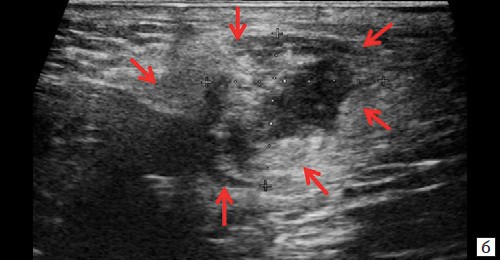

Описываемое образование прилежит к передне-боковой утолщенной стенке анального канала, нечетко от нее дифференцируется (см. рис. 1, а, б). По периферии образования – выраженная сосудистая реакция (см. рис. 1, в). По периферии образования ближе к ягодичной области – формирующийся свищевой ход размером 1,3×0,6×0,6 см (см. рис. 1, г).

Рис. 1. а, б – В-режим. В перианальной области слева на глубине 0,6 см от поверхности кожи определяется гипоэхогенное жидкостное образование с четкими неровными контурами с наличием неоднородного гиперэхогенного подвижного содержимого размером 3,9×2,1×1,9 см, объемом 8,24 мл с утолщенными до 0,3 см стенками. Описываемое образование прилежит к передне-боковой утолщенной до 1,0 см стенке анального канала, нечетко от нее дифференцируется (стрелки);

г – В-режим. По периферии образования ближе к ягодичной области – формирующийся свищевой ход размером 1,3×0,6×0,6 см (стрелки).